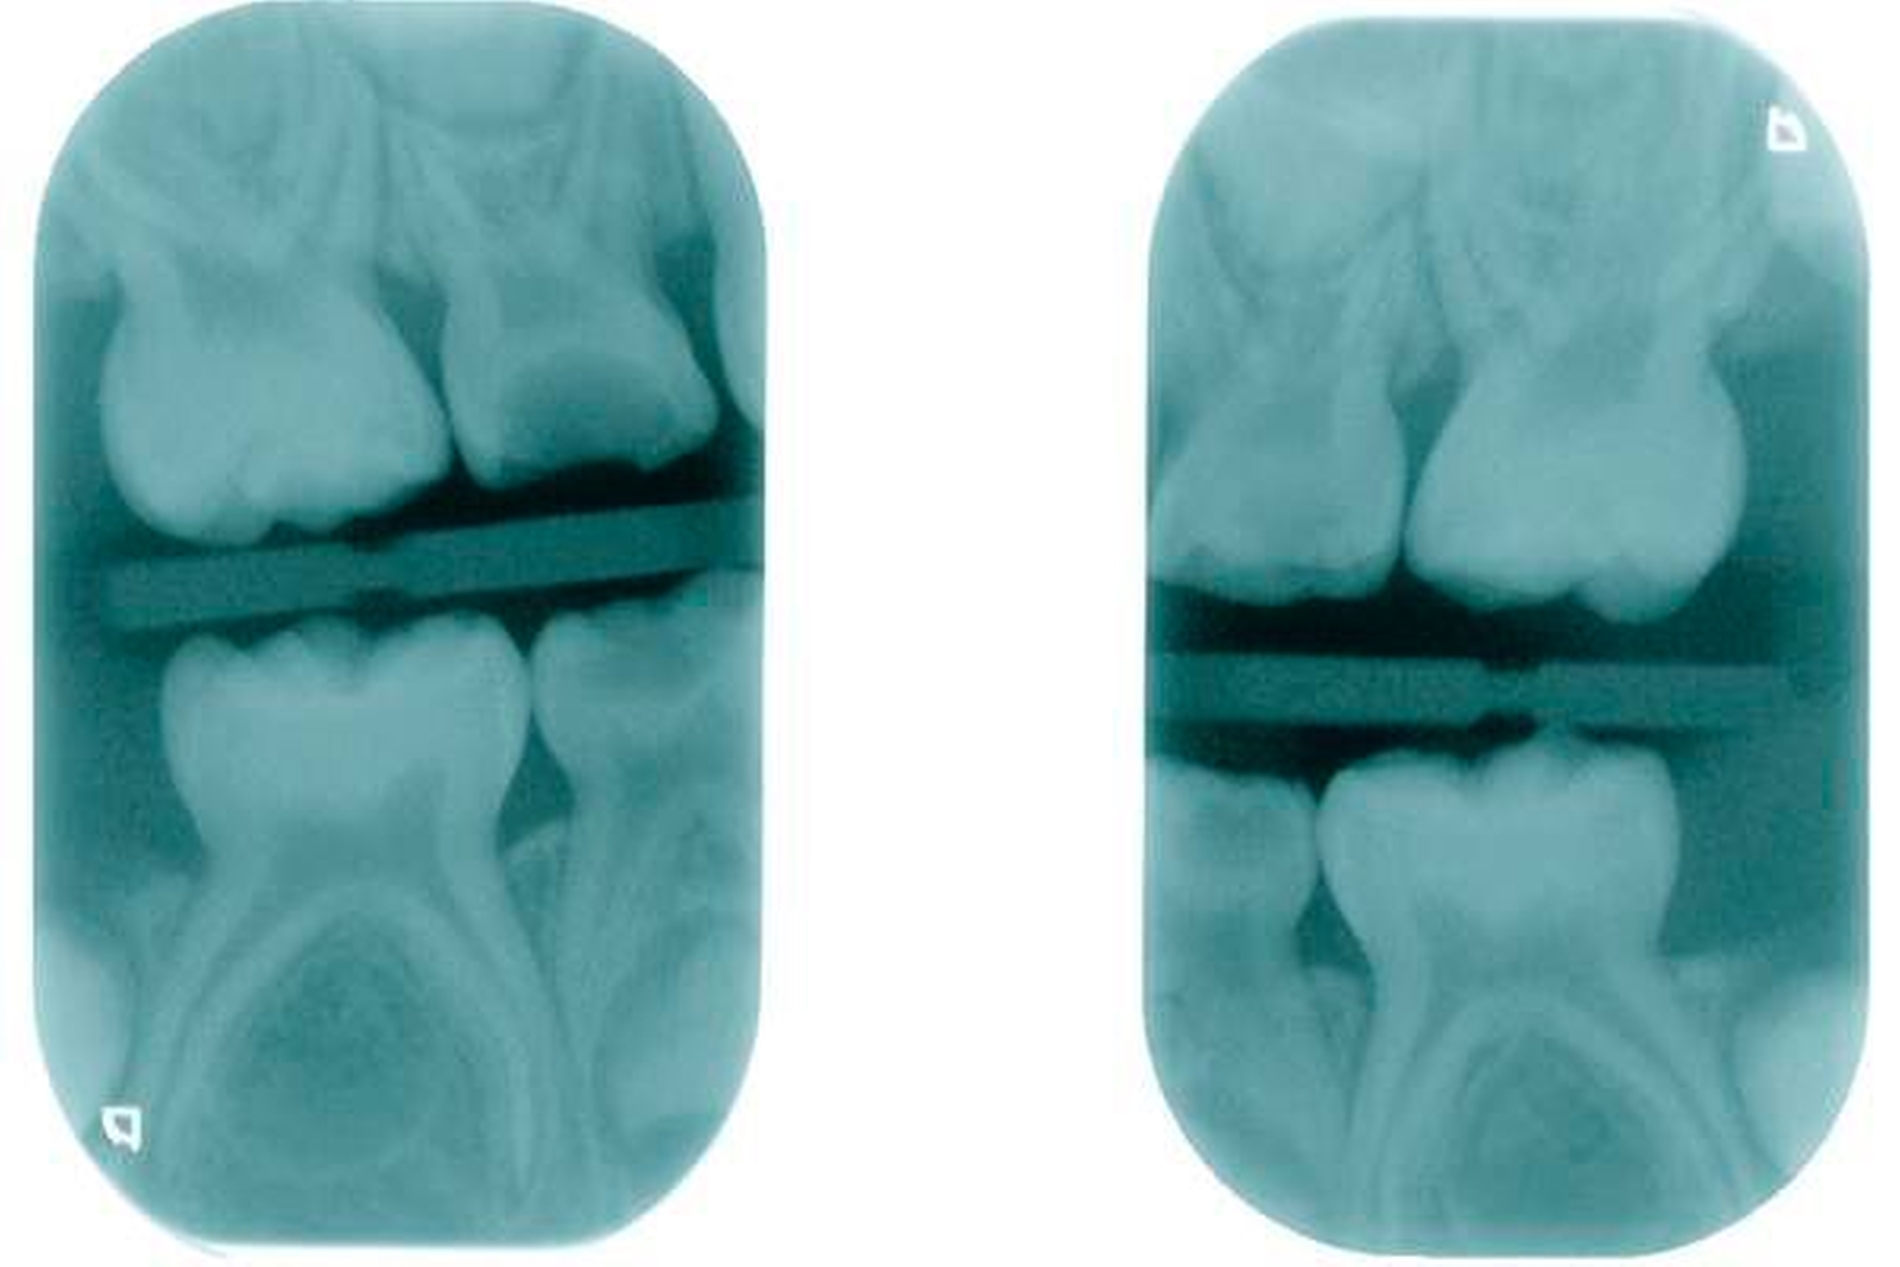

Zweiter Befund nach drei Jahren:Im April 2011 stellte sich der Patient erneut im ZFZ vor. Mittlerweile war der Patient sieben Jahre alt und im beginnenden Wechselgebiss zeigten sich Schmelzhypoplasien der Sechsjahresmolaren (Abbildungen 3 bis 5). Da die Zähne starke Empfindlichkeiten und zunehmende Substanzverluste trotz versuchter Fissurenversiegelungen aufwiesen, hat der Hauszahnarzt mit den Eltern entschieden, diese weiter versorgen zu lassen. Somit wurde der Patient wieder ans ZFZ überwiesen zur erneuten ITN-Behandlung.

Aufgrund der noch nicht eindeutigen Gebissentwicklung des Patienten und der Tendenz zum Engstand wurde in Absprache mit den Eltern, dem Hauszahnarzt und dem Kieferorthopäden die Entscheidung getroffen, dass die stärker betroffenen und sehr empfindlichen Zähne 26, 36 und 46 mit Stahlkronen versorgt und Zahn 16 neu versiegelt werden sollte (Abbildungen 6 bis 8).

Leider ist die Präparation der Sechsjahrmolaren oft zeitraubender und geht meist mit erheblichem Substanzverlust einher. Nach versuchter schonender tangentialer Präparation mesial und distal sowie Reduktion der Höhe um circa 1,5 mm wird die entsprechende Kronengröße ausgewählt. Diese kann noch durch Kürzen oder Biegen des Randes individualisiert werden. Wichtig ist es, vor dem definitiven Einsetzen der Kronen den korrekten Sitz mittels Röntgenbild zu überprüfen. Bedingt durch das Fehlen eines basalen Schmelzwulstes lässt sich die Konfektionskrone trotz eines elastischen Federrandes auf dem konisch beschliffenen Zahn nur schwer fixieren. Störungen der Okklusion sind die Norm (noch unproblematisch im beginnenden Wechselgebiss), ein exakter Randschluss ist praktisch nicht zu erreichen. Insbesondere interdental, am Übergang zwischen Krone und Zahn, sind in jedem Fall Retentionsnischen vorhanden, die die Ansammlung von Plaque begünstigen. Folgeproblem ist Sekundärkaries und eine dauerhafte Irritation des marginalen Parodontiums. Verbleiben die Kronen über das 15. Lebensjahr hinaus im Mund, muss mit zum Teil erheblichem Knochenabbau gerechnet werden!